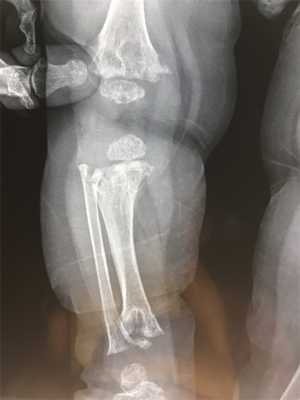

Клиническая картина включает в себя: неполное разгибание в локтевом суставе, килевидную грудную клетка, искривление ног, удлинение малоберцовой кости относительно большеберцовой. У больных наблюдаются укорочение и утолщение кистей, разболтанные суставы кистей и стоп, недоразвитые ногти. При рентгенологическом исследовании выявляются изменения, названные метафизарным дизостозом: расширенные метафизы с фестончатым, неровно склерозированным краем. Биопсия выявляет гипоплазию хрящей. Волосы у больных тонкие, короткие, редкие, светлые. Поражаются также брови и ресницы. У многих больных имеются иммунологические дефекты, нарушается как клеточный, так и гуморальный иммунитет. Они чувствительны к инфекциям, могут иметь лимфопению, нейтропению, анемию. У некоторых больных нарушается кишечное всасывание, а также у них повышен риск опухолеобразования, преимущественно лимфом.

Осложнениями синдрома являются артриты, килевидная деформация грудной клетки вследствие раннего закрытия швов грудины и эквиноварусные деформации стоп. К характерным рентгенологическим признакам относится расширение метафизов в области коленных суставов и средних фаланг кистей и стоп, а также умеренное уплощение и недоразвитие тел позвонков (у взрослых эти изменения исчезают).

Метафизарная хондродисплазия (хряще-волосяная гипоплазия, СНН; тип Мак-Кьюсика, MIM 250250) - форма карликовости с короткими конечностями, возникающей в результате скелетной дисплазии. Скелетные особенности включают неполное разгибание в локтевом суставе, килевидная грудная клетка, искривление ног, удлинение малоберцовой кости относительно большеберцовой. У больных наблюдаются укорочение и утолщение кистей, разболтанные суставы кистей и стоп, недоразвитые ногти. При рентгенологическом исследовании выявляются изменения, названные метафизарным дизостозом: расширенные метафизы с фестончатым, неровно склерозированным краем. Биопсия выявляет гипоплазию хрящей. Волосы у больных тонкие, короткие, редкие, светлые. Поражаются также брови и ресницы. У многих больных имеются иммунологические дефекты, нарушается как клеточный, так и гуморальный иммунитет. Они чувствительны к инфекциям, могут иметь лимфопению, нейтропению, анемию. У некоторых больных нарушается кишечное всасывание, а также у них повышен риск опухолеобразования, преимущественно лимфом.

Для пациентов с типом MакКьюзика характерны хроническая анемия, патологии кишечника. На рентгеновских снимках заметно увеличение метафизов в области коленного сустава. В детском возрасте нередко встречается двояковыпуклое строение позвонков, которое постепенно исчезает после взросления.